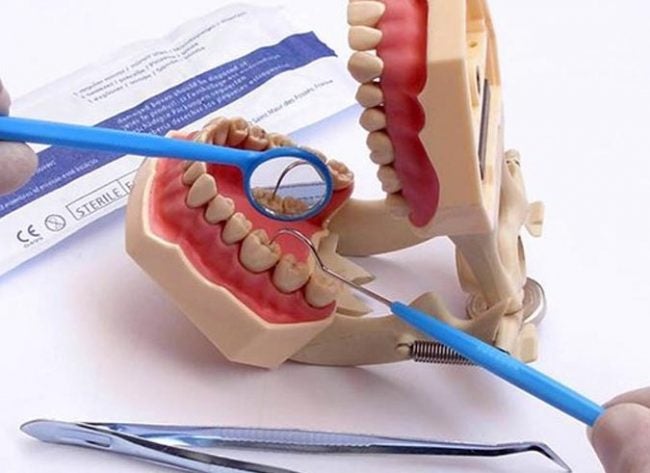

Perda do esmalte dentário | Entenda quais são as causas

A perda do esmalte dentário é um problema sério que afeta muitas pessoas, sendo uma das principais causas do retorno do paciente ao consultório odontológico. Por ajudar a proteger os dentes, o esmalte dentário pode sofrer danos devido ao processo de mastigação e trituração dos alimentos. Embora o esmalte seja um protetor rígido dos dentes,…